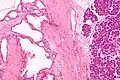

![]() Micrografía mostrando un cistoadenoma seroso del páncreas. H&E stain. | ||